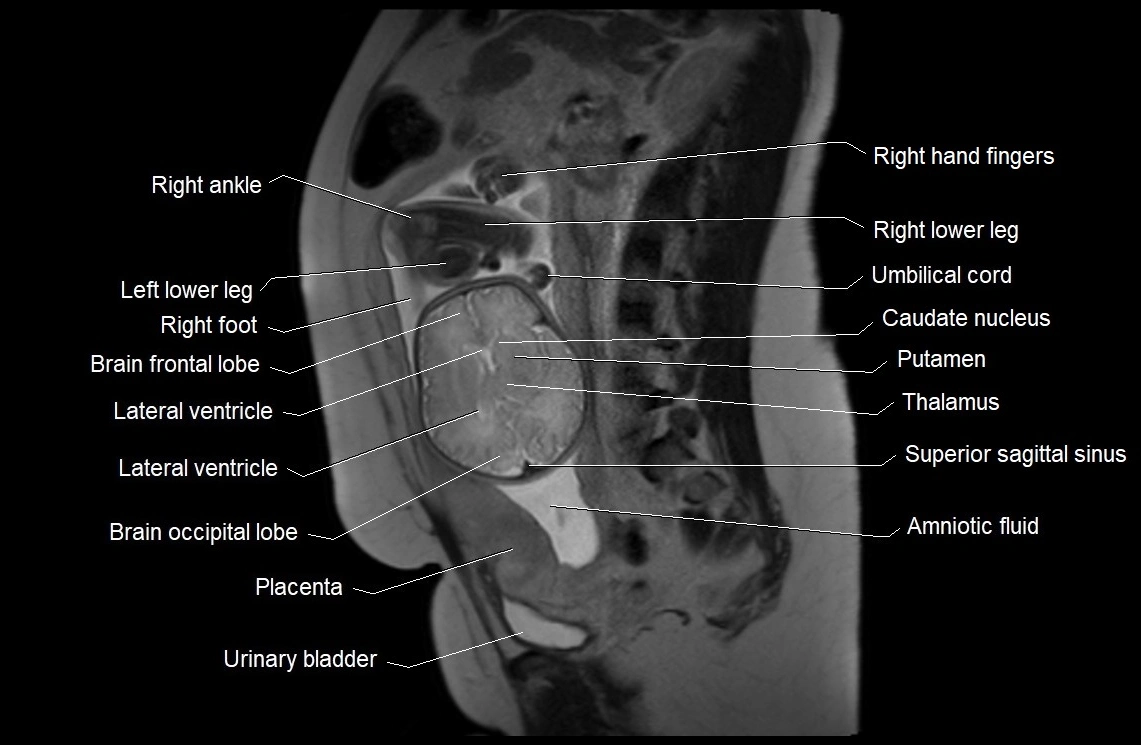

MRI Appearance

T2 HASTE (T2 GRE):

• Amniotic fluid shows very bright hyperintense signal

• Provides natural contrast against fetus and placenta

• Small particles (vernix) may appear as scattered hypointense foci within bright fluid

T1 GRE:

• Amniotic fluid shows low signal intensity (dark)

• Hemorrhage, infection, or proteinaceous content may cause focal or diffuse high signal intensity

MRI image

image